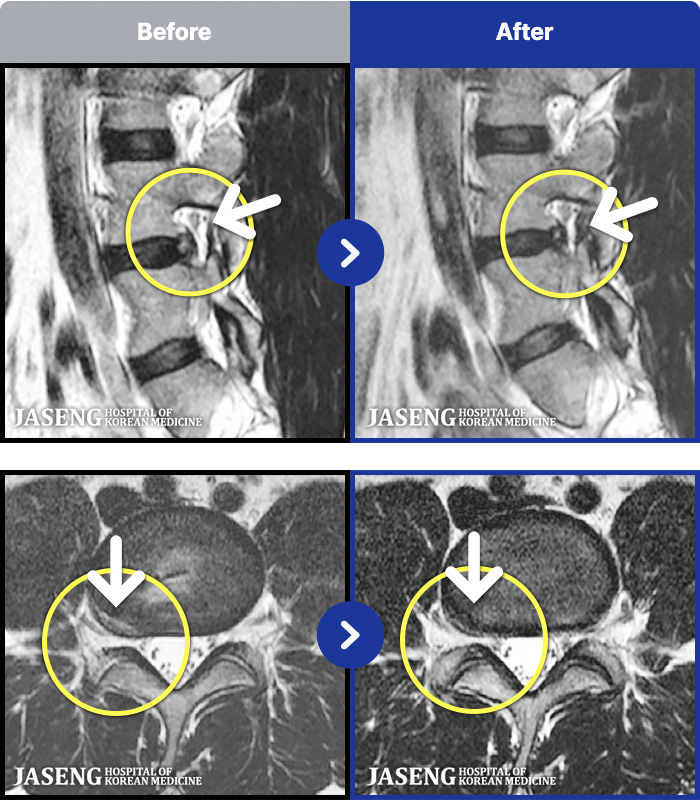

1,296 MRI ũ ʸ Ȯϼ.

ȯںп Ǹ ǿ ԿǾ, ο ġ ۿ Ƿ ġḦ Ͻñ ٶϴ.